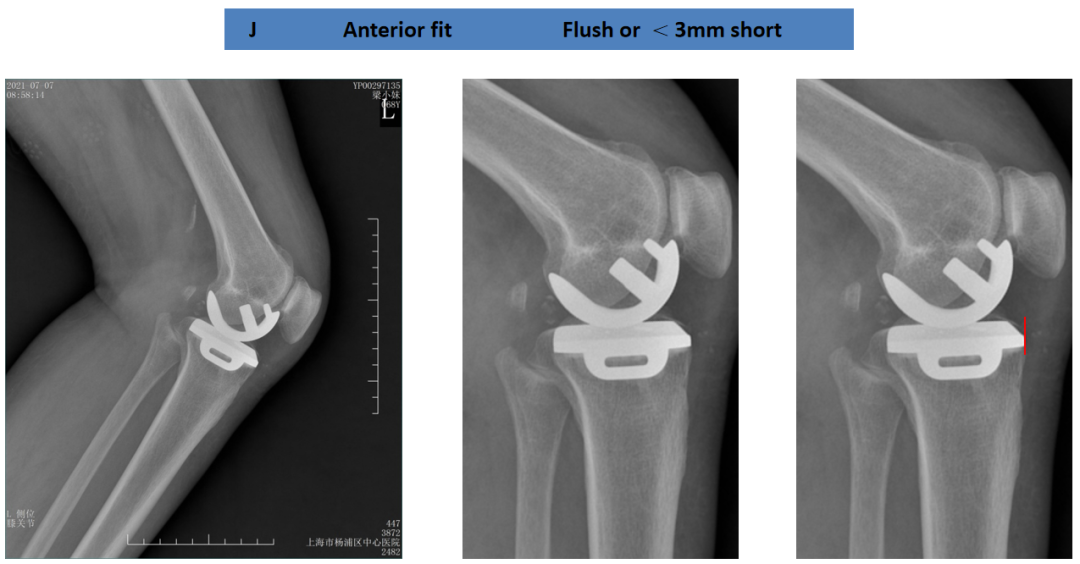

胫骨平台前后覆盖(矢状位)

胫骨假体完全覆盖胫骨截骨面:后缘齐平,假体完全覆盖胫骨平台。

胫骨假体完全覆盖胫骨截骨面:前缘齐平,假体完全覆盖胫骨平台。

胫骨平台后缘覆盖不足

胫骨假体对胫骨截骨面的前后覆盖:未完全覆盖胫骨平台,前缘齐平,后缘短2mm。